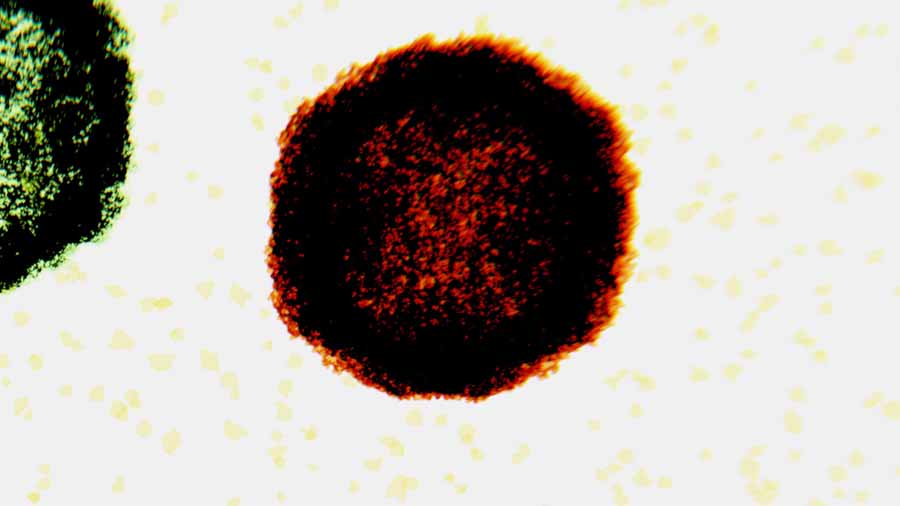

EV-D68 is part of a family of viruses known as enteroviruses, which are named for the transmission route, through the intestines. They are mainly spread through unwashed hands but can also be spread through respiratory droplets caused by sneezing or coughing.

Polio is one of the more severe enteroviruses, which otherwise typically cause only mild symptoms.

In most cases, non-polio enteroviruses, including EV-D68, cause mild respiratory illness. But in some cases, people infected with EV-D68 develop a condition called acute flaccid myelitis (AFM), which causes sudden limb weakness, slurred speech, and pain in the limbs and back. In some, it can progress to paralysis that includes respiratory paralysis, which is life-threatening, and in worse cases, the paralysis may become permanent.